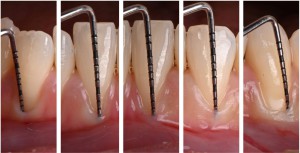

※歯肉退縮量の測定

今回は、複数の歯で歯ぐきが下がっている状態がみられたため、専用の器具(プローブ)を用いて、それぞれの歯の歯ぐきの下がり具合を測定しました。

また、測定の際に器具が歯ぐきの中で透けて見える所見があり、歯ぐきの厚みが比較的薄い状態である可能性が示唆されました。